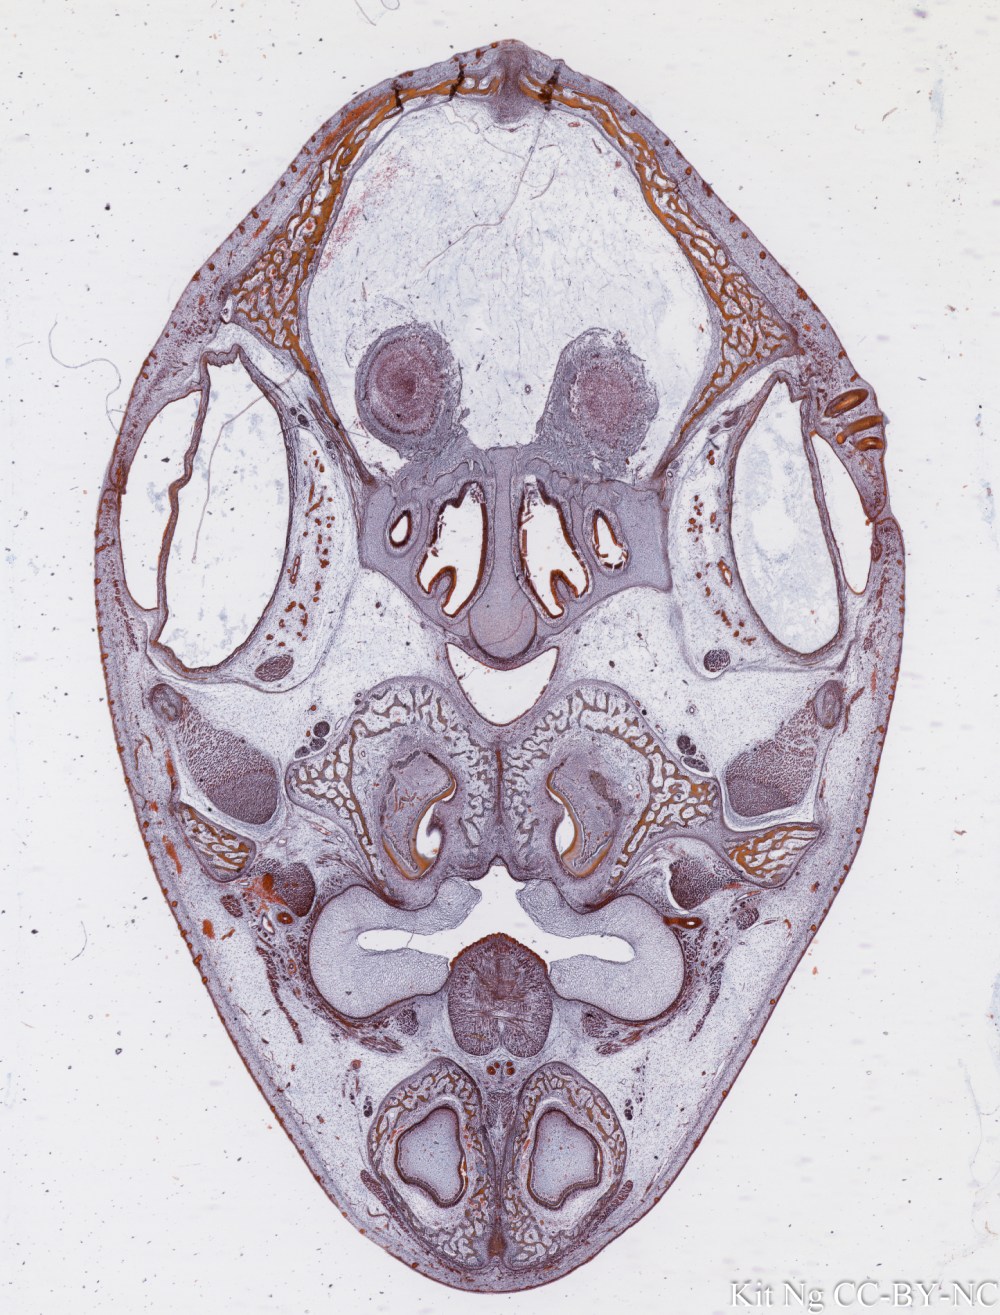

Images Membranous Bone Development in Fetal Skull From SMC collection. Membranous Bone in Fetal Skull (TM: 2.5x, picture taken with a Nikon Coolscan V Slide scanner from a damaged slide) Share this: Email a link to a friend (Opens in new window) Email Share on X (Opens in new window) X Share on Facebook (Opens in new window) Facebook Like Loading...